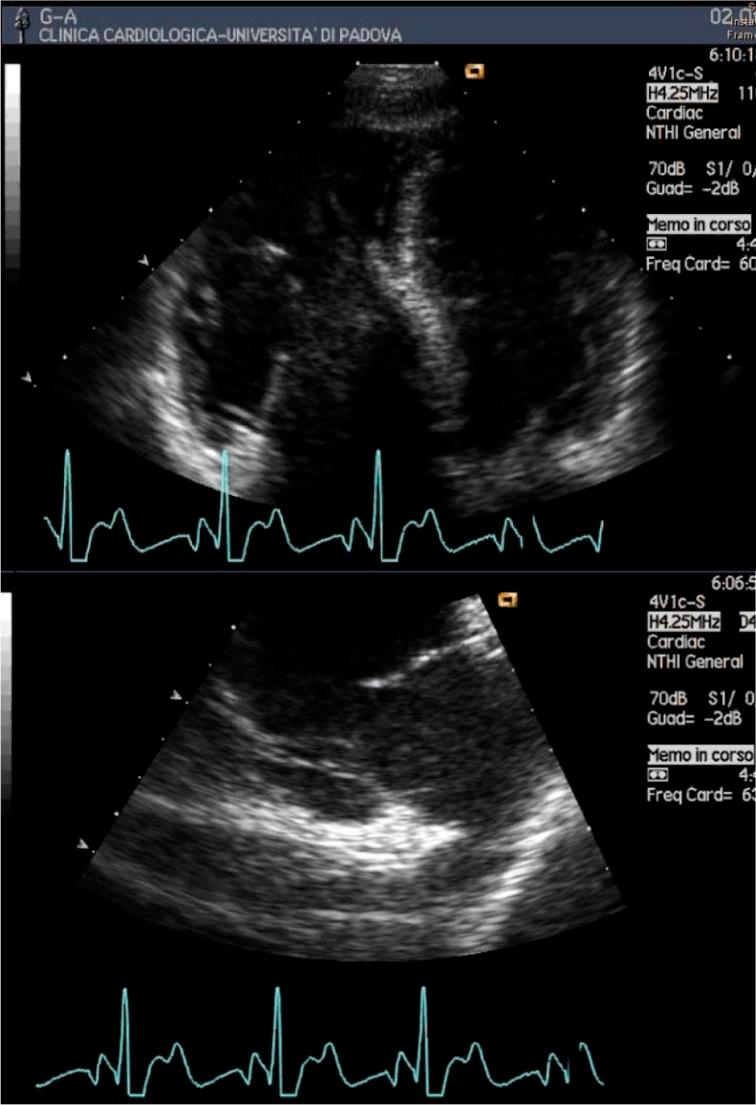

Science and practice of arrhythmogenic cardiomyopathy: A paradigm shift.

Glob Cardiol Sci Pract. 2013 Nov 1;2013(1):63-79. doi: 10.5339/gcsp.2013.8. eCollection 2013.